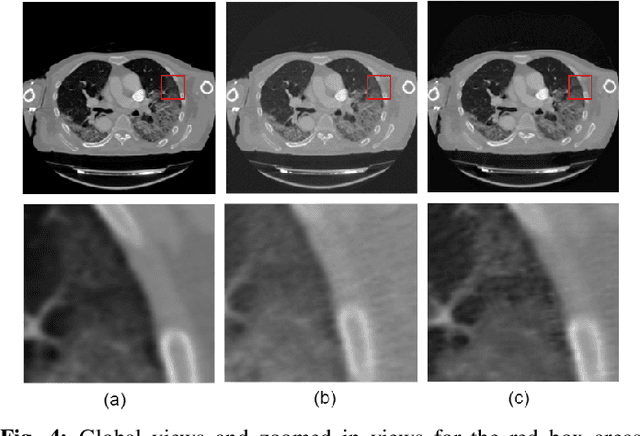

We present a deep-learning based computing framework for fast-and-accurate CT (DL-FACT) testing of COVID-19. Our CT-based DL framework was developed to improve the testing speed and accuracy of COVID-19 (plus its variants) via a DL-based approach for CT image enhancement and classification. The image enhancement network is adapted from DDnet, short for DenseNet and Deconvolution based network. To demonstrate its speed and accuracy, we evaluated DL-FACT across several sources of COVID-19 CT images. Our results show that DL-FACT can significantly shorten the turnaround time from days to minutes and improve the COVID-19 testing accuracy up to 91%. DL-FACT could be used as a software tool for medical professionals in diagnosing and monitoring COVID-19.